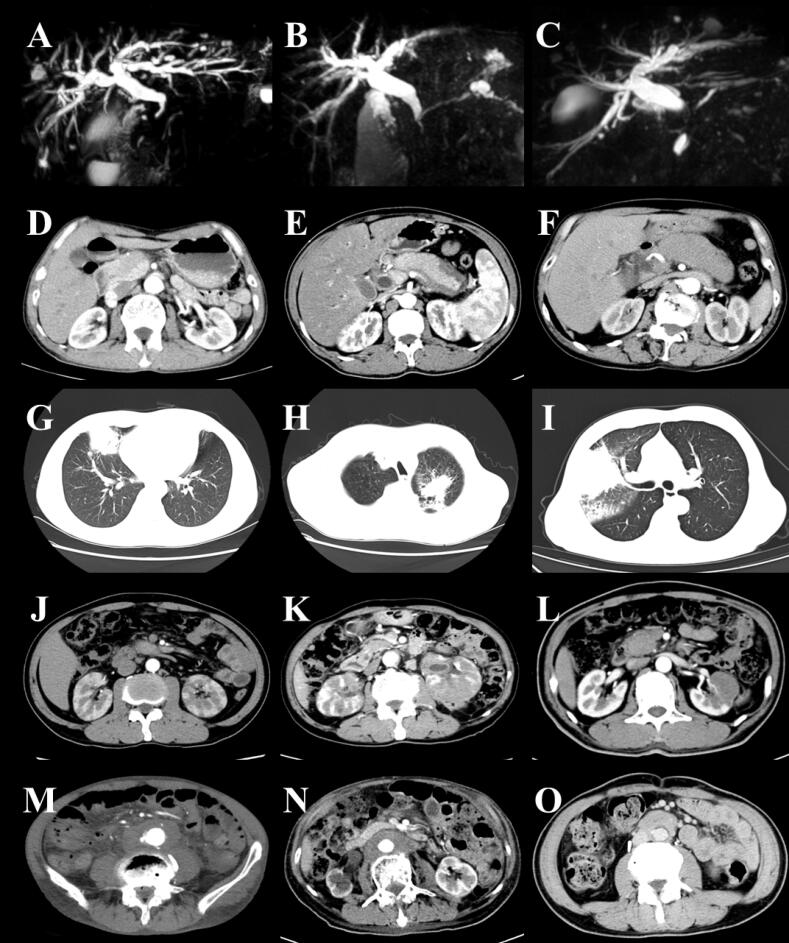

Background: Immunoglobulin G4-related disease (IgG4-RD) is a rare, chronic inflammatory condition characterized by fibrosis and tendency for multi-organ involvement. This study aims to analyze the clinical characteristics associated with multi-organ versus single-organ involvement in IgG4-RD, thereby enhancing clinicians' understanding of the differences between these two patient groups and ultimately improving patient prognosis.

Methods: We performed a retrospective analysis of clinical data from 82 patients diagnosed with IgG4-RD admitted to Yichang Central People's Hospital between January 2019 and December 2024.

Results: Among the 82 patients diagnosed with IgG4-RD, 47 patients (57.32%) exhibited involvement of multiple organs. The incidence of multi-organ involvement was significantly higher in male patients than female patients [63.49% vs. 36.84%, odds ratio (OR): 2.98, 95% confidence intervals (CI): 1.03-8.64, P<0.05]. The misdiagnosis rate in the multi-organ involvement group was significantly higher than that in the single-organ involvement group (29.79% vs. 8.57%, OR: 4.525, 95% CI: 1.19-17.26, P<0.05). In patients with involvement of the pancreas (72.50% vs. 42.86%, OR: 3.515, 95% CI: 1.39-8.86, P<0.05), or lymph nodes (83.72% vs. 28.21%, OR: 13.091, 95% CI: 4.50-38.11, P<0.05), the incidence of additional organ involvement was significantly higher than those with involvement of other organs. The eosinophil percentage [median difference (Hodges-Lehmann): 1.60%, 95% CI: 0.40-2.80, P<0.05], absolute eosinophil count [median difference (Hodges-Lehmann): 0.10×109/L , 95% CI: 0.30-0.16, P<0.05], serum immunoglobulin G (IgG) levels [median difference (Hodges-Lehmann): 4.10 g/L, 95% CI: 0.10-7.80, P<0.05], and erythrocyte sedimentation rate (ESR) [median difference (Hodges-Lehmann): 30.50 mm/h, 95% CI: 13.00-48.00, P<0.05] were significantly higher in the multi-organ involvement group compared to the single-organ involvement group. There was a positive correlation between the number of involved organs and ESR (r=0.404, 95% CI: 0.166-0.597, P=0.001), eosinophil percentage (r=0.287, 95% CI: 0.068-0.480, P=0.009), absolute eosinophil count (r=0.293, 95% CI: 0.075-0.485, P=0.007), serum IgG levels (r=0.370, 95% CI: 0.130-0.570, P=0.003), and serum IgG4 levels (r=0.370, 95% CI: 0.130-0.570, P=0.003).

Conclusion: The clinical features associated with multi-organ involvement in IgG4-RD are characterized by significant diversity and complexity. Clinicians must enhance their understanding of the characteristics associated with multi-organ involvement to more effectively improve patient prognosis.